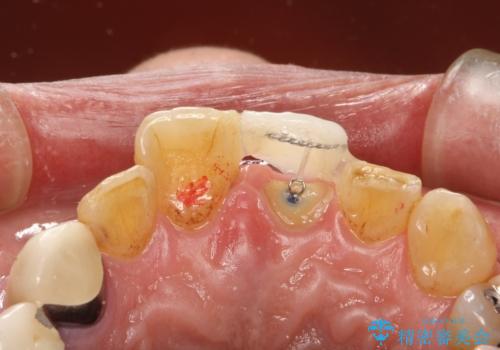

左上1が水平的に割れている状態で、歯冠を取り除くと神経が露出しており、唇側はかなり歯肉縁下で破折しており、そのままではかぶせものを入れるのは難しい状態でした。

抜かずになるべくその歯を残して使っていきたいとのことで、

根管治療をした上で歯を引っ張りだして(エクストリュージョン)、その後、骨外科にて歯周組織を整えた上で、かぶせものを入れていく治療計画をたてました。